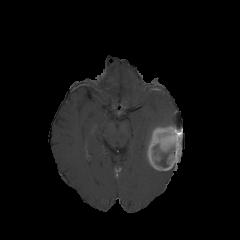

We argue that the sub-optimal paradigm of processing different abstractions within a single CNN pipeline can be remedied through the effective processing of information in a structured manner. Consequently, we devise strategies for disentangling the edge and texture information within a single training pipeline. Figure 2 illustrates how our proposed module, dubbed EG-CNN, can be paired with any existing CNN encoder-decoder to improve segmentation quality near intensity edges. We have applied our EG-CNN to the tasks of brain and liver tumor segmentation in medical images (Figure 3).

(1) Brain MR (2) Liver MR (3) Liver CT (4) Lung CT